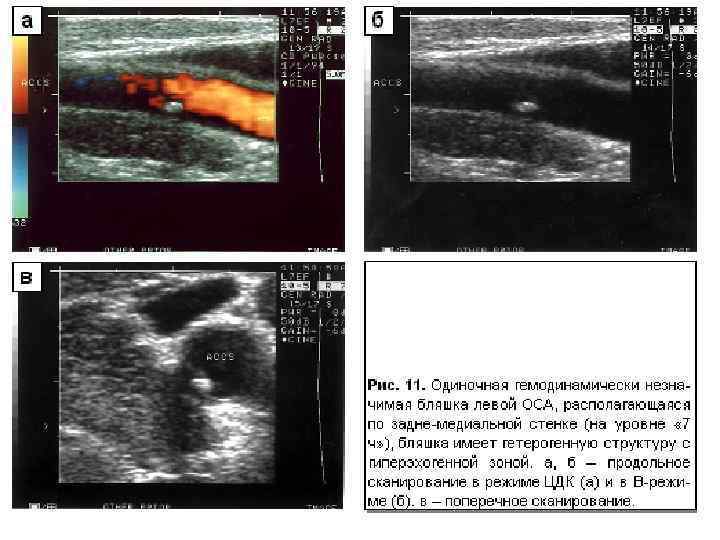

Диагностическая информативность ¡ ¡ ¡ Размеры артерий и вен; Скорости и характер движения крови; Толщина комплекса интима-медия (в норме – до 0, 8 мм в ОСА), наличие бляшек; Наличие извитостей, аневризм и стеноза артерий; Наличие тромбов, перфорантных вен при варикозной болезни, регургитации на клапанах Аномалии развития артерио-венозного русла